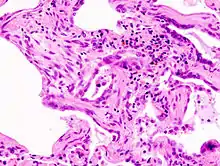

Coloration à l'hématoxyline et à l'éosine (HE).

Le diagnostic se fait après enquête étiologique négative grâce à la combinaison de critères scanographiques et éventuellement anatomopathologies (après biopsie chirurgicale pulmonaire). L'aspect histologique typique est celui d'une UIP (de l'anglais « Usual Interstitial Pneumonia ») ou PIC en français (pneumonie interstitielle usuelle) qui se caractérise par une fibrose disséminée, des amas de fibroblastes, une distorsion architecturale marquée dans les régions septales et pleurales avec une structure en nid d'abeilles du poumon. Le modèle de l'UIP est caractéristique mais pas spécifique, et se présente dans d'autres variétés. Sur le scanner haute résolution, on parle aussi dans les formes typiques de tableau de PIC avec association de réticulations (dessins de réseaux et de lignes), d'élargissement des bronches par tractions, d'opacités floues dites en verre dépolien général peu étendues, d'aspect en nid d'abeilles dans les bases et les régions périphériques sous pleurales (destruction irréversible de l'architecture normale du poumon). Ces modifications sont le plus souvent bilatérales mais asymétriques et dans les bases des poumons.